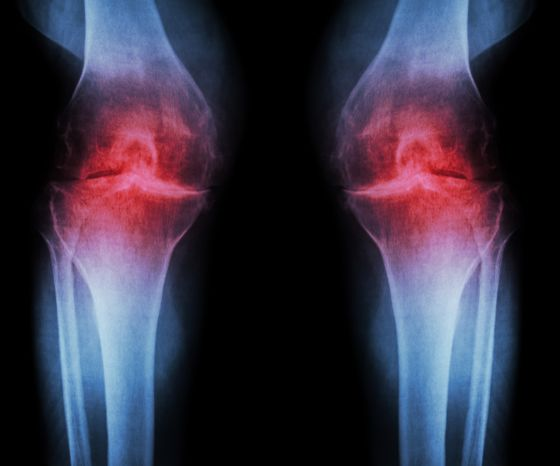

影像学检查指南:X光、MRI到底能看出什么“名堂”?

当你的关节开始出现不明原因的疼痛、弹响或者僵硬时,去医院挂号,医生最常开出的两张“通往真相的门票”就是:X光片和核磁共振(MRI)

一、 X光:看的是“间隙”里的秘密

很多人误以为X光能直接看到软骨

其实,在X光的成像原理中,软骨是“透明”的

1. 为什么X光只看“间隙”?

X光的穿透力与物质密度有关

骨头密度大,吸收射线多,在底片上显现为白色;而软骨、韧带、积液这些含水量高的组织,密度低,射线几乎全穿过去了,在底片上就是一片漆黑

逻辑递进:

既然软骨看不见,医生怎么判断它磨损了呢? -> 看间隙

想象一下两块坚硬的砖头(骨头)之间垫了一层厚厚的透明橡胶垫(软骨)

X光下,你只能看到两块砖头,它们中间空出了一段距离

健康状态: 砖头之间的“黑缝”很宽,说明橡胶垫很厚

骨关节炎状态: “黑缝”变窄了,甚至两块砖头快撞在一起了,说明橡胶垫(软骨)已经磨损殆尽